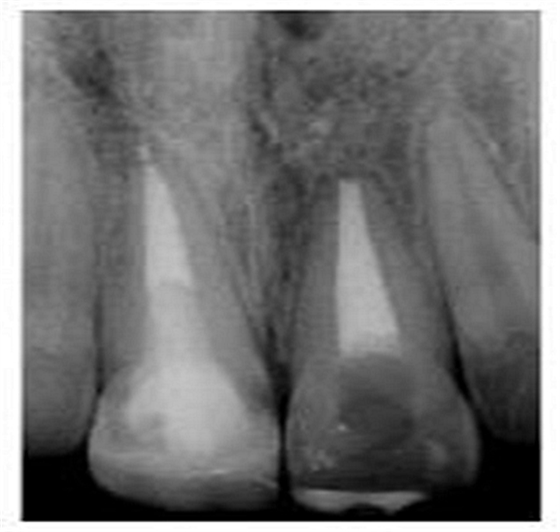

切端則采用透明樹脂,最后使用釉質樹脂(Amaris, VOCO, Cuxhaven, Germany)。21的樹脂修復采用類似的方式。修復初步成型,拋光,恢復干燥牙釉質的顏色。攝片顯示樁在根管內位置合適(圖15)。最后一次復診精修、拋光充填體,完成治療。